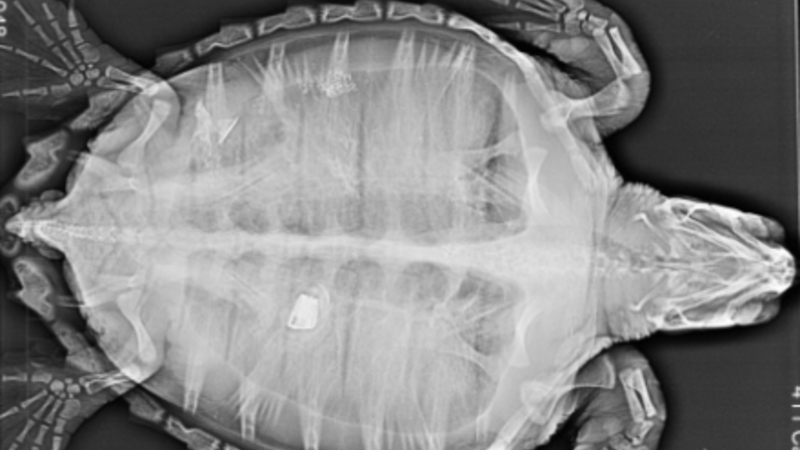

Dyrlægerne hos akvariet gjorde store øjne, da de gav skildpadden en ultralydsscanning og så, hvad der lå og rumsterede i dens tarm.

Det lille dyr havde nemlig gumlet et stykke af en lighter i sig, og det kom der et noget spøjst røntgenfotografi ud af:

Lægerne var selvfølgelig nervøse for, at fyrtøjet skulle gøre skade på padde, men heldigvis gik der ikke længe, før lighteren kom ud ganske naturligt:

Nederst i billedet kan man se det lille stykke lighter, som drillede padden